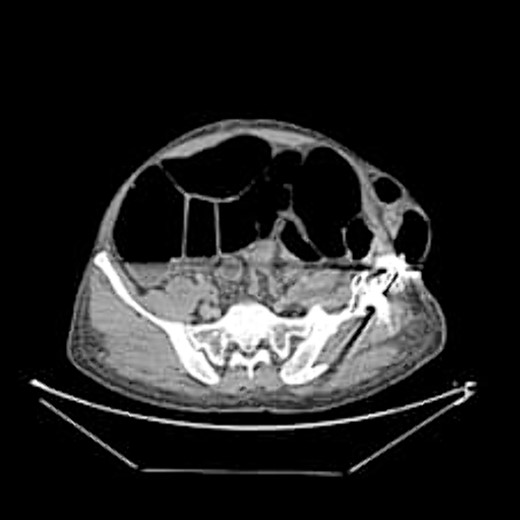

The CT abdomen pelvis (Figs 5 and 6) showed signs of bowel obstruction signs, along with an internal hernia at the place of the prior ORIF surgery. These findings were thought to be the core cause of the patient’s presentation in align with the taken history, physical examination of the patient.

The preferred imaging method is computed tomography. While ultrasound is a low-cost, low-risk alternative for assessing these hernias, it does not reveal concomitant abdominal illness and is used less frequently in clinical settings [22, 23]. Conventional X-rays revealed dilated bowel segments. The computed tomography (CT) picture indicated several dilated colonic segments as well as a hernial defect on the left side of the abdomen. Moreover, ultrasonography of the abdomen and pelvis revealed a moderate reactive free fluid accumulation in the pelvis and a bowel loop imprisoned in the apparent bulge.